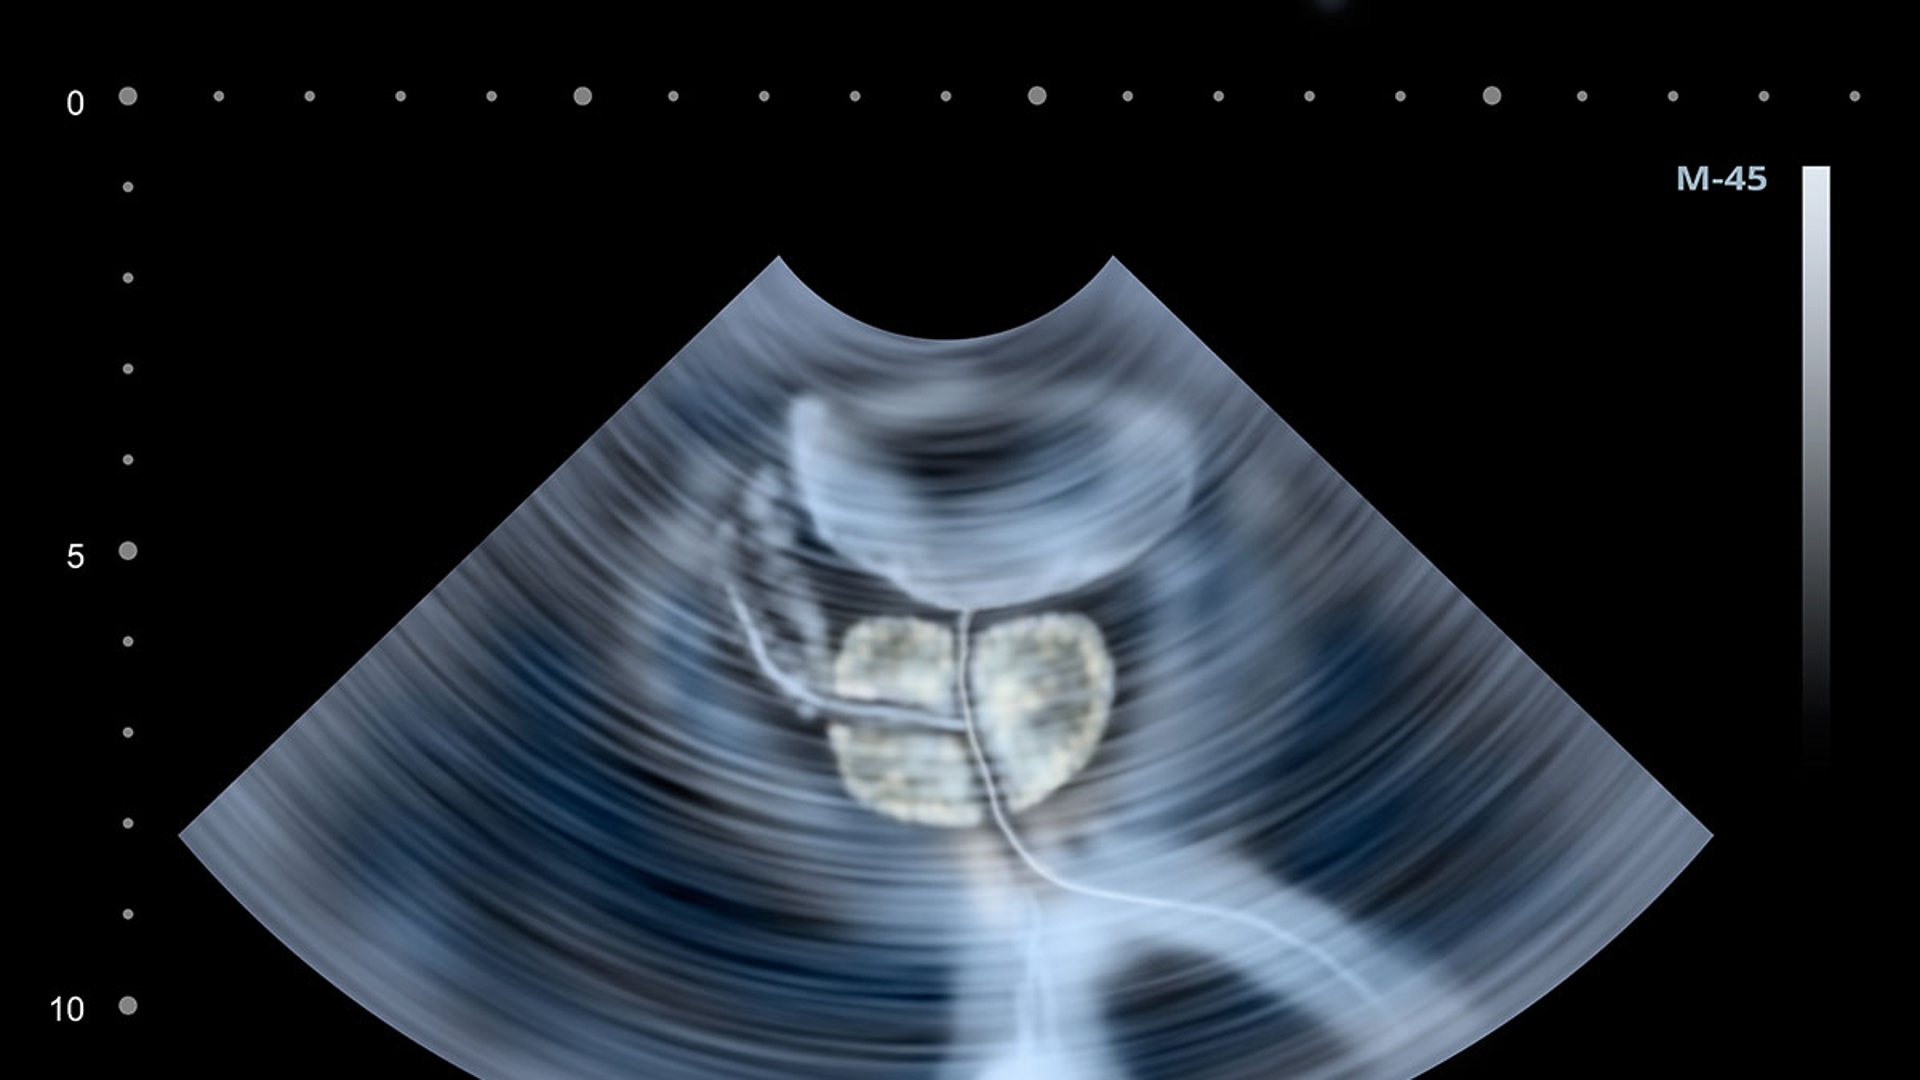

Il chirurgo, tramite un’interfaccia digitale, disegna il piano di resezione sulla mappa anatomica della prostata. Il robot esegue quindi l’ablazione con una precisione millimetrica, rimuovendo solo la parte ipertrofica. L’intervento dura circa cinque minuti, viene effettuato in anestesia leggera e consente di dimettere il paziente in 24-48 ore, spesso senza necessità di catetere. Inoltre, l’accurata pianificazione preoperatoria prevede ecografia, uroflussometria e dosaggio del PSA per individuare i candidati ideali alla procedura.